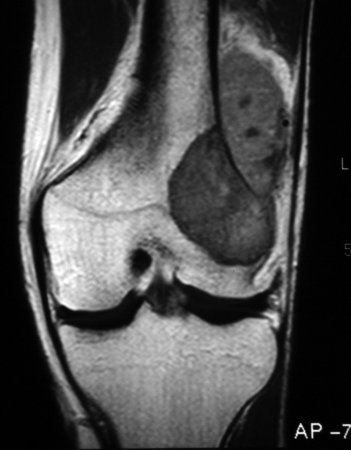

Osteossarcoma

Ressonância nuclear magnética (RNM), incidência coronal; osteossarcoma do fêmur distal mostrando sinal de baixa intensidade; imagem ponderada em T1; também é visualizada extensão tumoral real intraóssea e extraóssea

Do acervo do Dr. Michael J. Klein e da Dra. Luminita Rezeanu